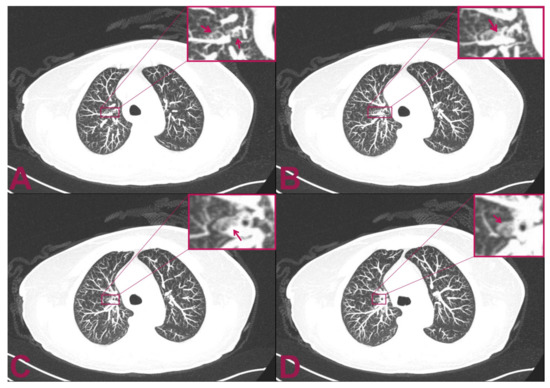

The postoperative course was regular, with no additional neurological deficits compared to preoperative. In the following days, we performed a total-body computed tomography (CT) scan that revealed a small, solid mass in the superior segment of the right upper lobe of the lung (Figure 3). Unfortunately, she presented a rapid worsening of her neurological status and prematurely died within three weeks due to a sudden increase in perilesional oedema at the bulb of the spinal cord, which compressed the respiratory centres.

Figure 3. Postoperative multilayer spiral CT scan of the chest with intra-venous administration of contrast medium. The patient is affected by intramedullary cervical metastasis from a primary small-cell neuroendocrine carcinoma of the lung. (A,B) Axial views show two small, rounded, and confluent nodules located at the level of the superior segment of the right upper lobe of the lung which have a maximum diameter of 9 × 3 mm. (C,D) The CT axial view shows an additional 2.5 mm abnormal small, solid nodular formation that is located caudally to the previously indicated nodules. The mass appears adherent to the bronchial tube and measures 8 mm in maximum diameter.